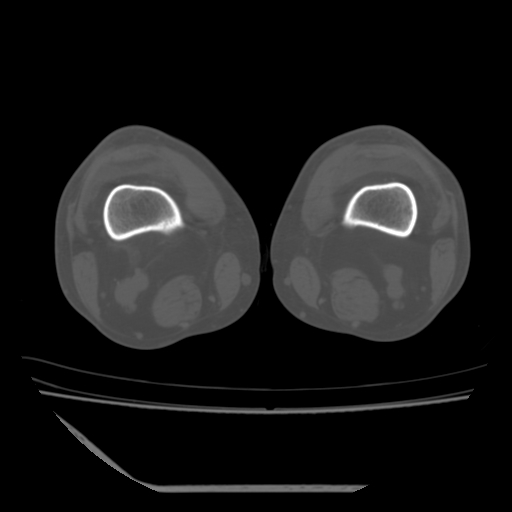

标题: CT13225:老年男性,左膝关节疼痛数月;请各位老师讨论。 [打印本页]

标题: CT13225:老年男性,左膝关节疼痛数月;请各位老师讨论。

骨质增生,骨性关节面硬化,关节积液,考虑退行性骨关节病

关节腔内少量积液,关节面退变。

双膝退变

骨质增生,骨性关节面硬化,关节间隙失常,关节积液,考虑退行性骨关节病.

这是由于两侧的肌肉不对称所致,加上扫描的平面也有些差异。请看示意图:

这个病例诊断:退行性骨关节炎